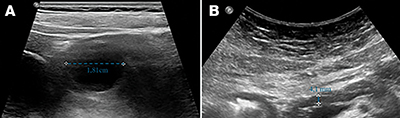

Az endoszkópos kezelések öt esetben jártak terápiás sikerrel; több betegnél különböző típusú endoszkópos eljárás kombinációjára volt szükség. A terápiás eszköztárban szerepelt az endoszkópos retrográd kolangiopankreatográfia (ERCP) során végzett törmelékextrakció, ballonos epeúti dilatáció és stentimplantáció (7. ábra). Ezenfelül endoszkópos ultrahang (EUS) által vezérelt tályogdrenázs is történt.

(A) A gyomor mögött 3 mm-es falú WON (60×90 mm); (B–C) Műanyag stentek a Vater-papillában